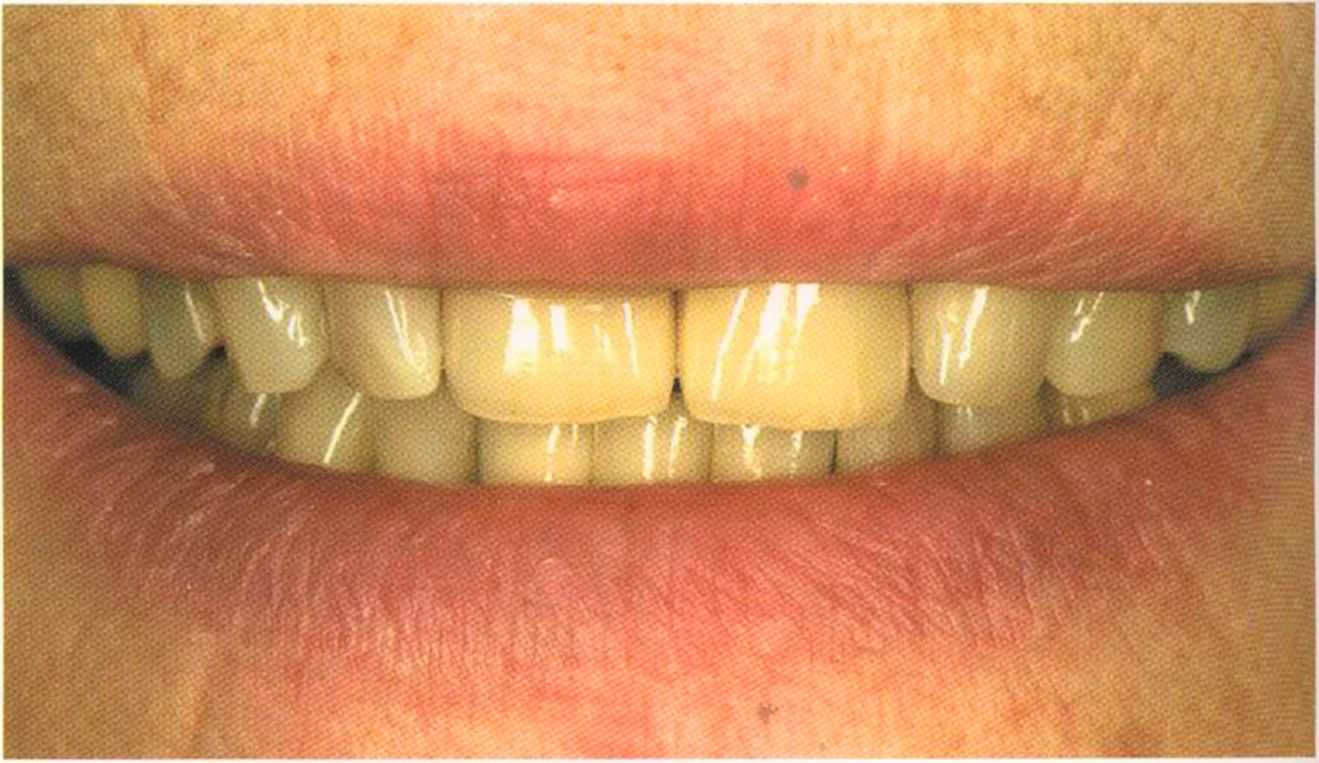

Окончательный результат и естественный цвет губ. Женщина была очень счастлива и довольна своим новым внешним видом. Наконец мечта осуществилась — нет больше этих щелей на видимом участке. Всей нашей команде было очень приятно видеть радость в ее глазах.